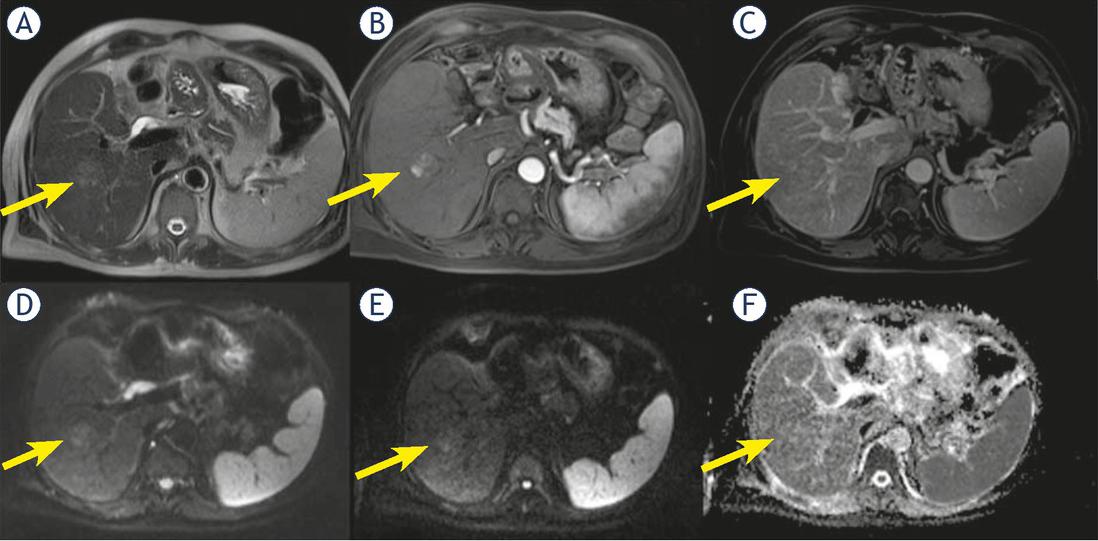

Twenty nodules (32.2%) showed an inhomogeneous hyperenhancement in arterial phase; 7 of them were cHCC-CCA (63.6% of cHCC-CCA) (Figure 1). We found this feature in 13 (25.5%) true HCC.

Man 56 y with combined hepatocellular-cholangiocarcinoma (cHCC-CCA) on VI hepatic segment. MRI study. The nodule is iso-hyperintense (arrow) in T2-W sequence (A), with inhomogeneous hypervascular appearance (arrow) during arterial phase of contrast study (B), without wash-out or capsule appearance (arrow) during portal phase of contrast study (C). The nodule shows restricted (arrow) diffusion (D, E and F) in diffusion weighted imaging (DWI) sequences.